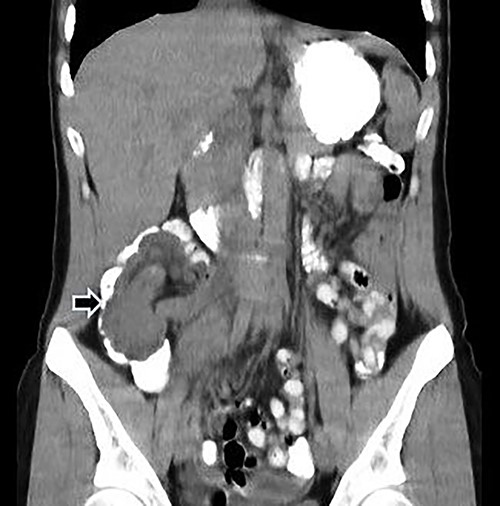

Computed tomography (CT) of the abdomen and pelvis with oral and intravenous contrast was performed (Fig. 1), and emergency surgery was decided due to the suspected ileocolic intussusception with a probable tumor origin (Fig. 2). The preoperative diagnoses were malignant cecum tumor (adenocarcinoma, sarcoma) or benign tumor (lipoma, villous tumor).

Abdominal CT with oral and IV contrast, coronal view; tumoral mass and intussusception (arrow).